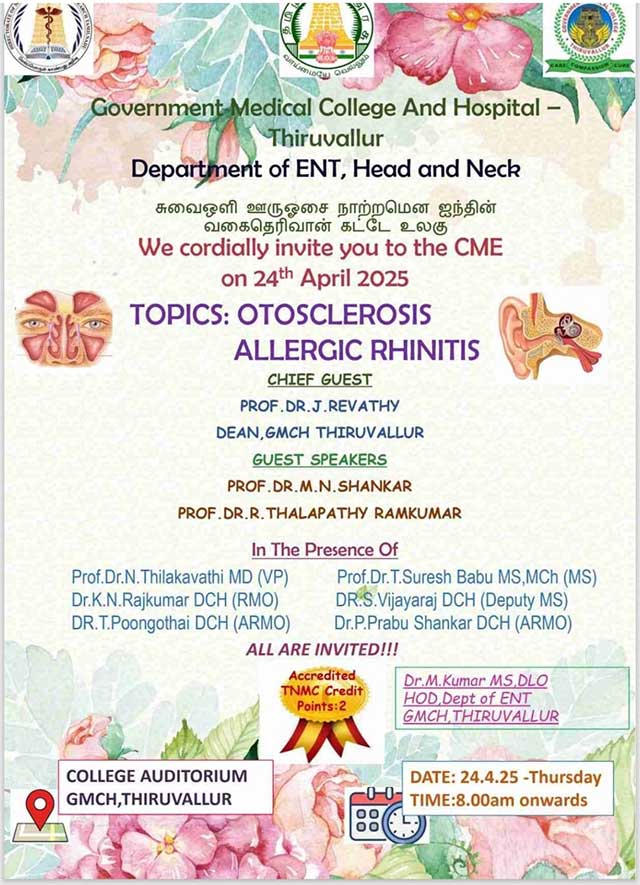

ENT CME ON OTOSCLEROSIS AND ALLERGIC RHINITIS: 24/04/2025

Topic |

Date |

| CEP- Otosclerosis and Allergic Rhinitis | 24-04-2025 |